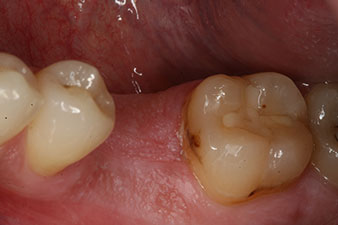

osificado de forma incompleta

Figura 2: Seis semanas después, se observó un alvéolo que solo estaba osificado de forma incompleta en el área de la raíz mesial.

No obstante, seis semanas después de la extracción, tras la disección del colgajo mucoperióstico, se observó una osificación incompleta en el área del antiguo alvéolo mesial.